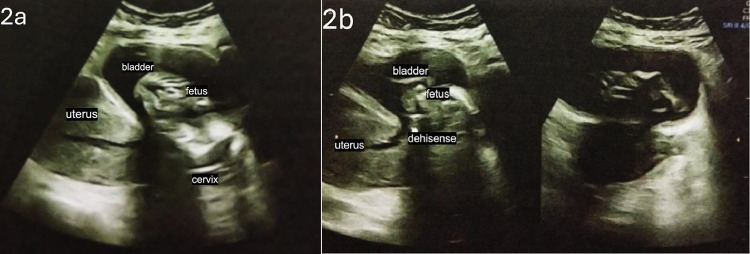

Vesicouterine fistula (VUF) is a rare form of urogenital fistula, accounting for approximately 4% of cases. It commonly arises as a complication of uterine interventions, especially previous cesarean sections (C-sections). Intravesical ectopic pregnancy complications are infrequent. We discuss a 39-year-old female with severe lower abdominal pain spreading to the flank, dysuria, hematuria, and urinary hesitancy one week after laparotomy for fetal demise at 17-18 weeks of gestation. A dead fetus in the urinary bladder along with the VUF was revealed in the imaging. The surgical operation identified a fistula between the posterior bladder wall and the lower uterine segment. Fetus evacuation and fistula repair were performed with symptom resolution achieved. A literature review was conducted and nine articles were extracted. These articles discussed the risk factors and complications of VUF. The articles, selected for relevance and quality, highlighted cesarean sections as the most common risk factor, with hematuria being the most frequent complication. Only a small number of cases had fetal migration into the bladder documented, showcasing its rarity. This case represents a rare complication of VUF: intravesical ectopic pregnancy into the bladder. Surgical intervention led to favorable outcomes and is consistent with findings in the reviewed literature. The rare complication of VUF such as intravesical ectopic pregnancy requires proper diagnosis and treatment. This case emphasizes the importance of surgical management in achieving successful outcomes for VUF and its complications.